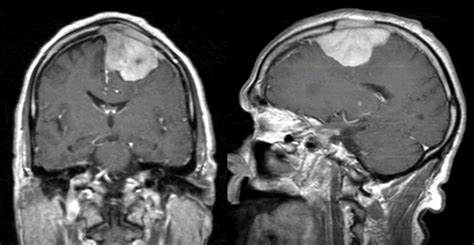

脑膜瘤是一种常见的脑瘤,它在脑膜(覆盖和保护大脑和脊髓的区域)中缓慢发展。大多数脑膜瘤是良性的,在大小和位置上差异很大。脑膜瘤严重吗?几乎90%的脑肿瘤都是良性的,手术可以治愈。生存期可以达到10年没有复发。良性脑膜瘤的良好预后和长期生存很普遍。

尽管它们很普遍,但多数脑膜瘤是由蛛网膜细胞产生的轴外良性缓慢生长的肿瘤。因此,许多脑膜瘤,包括相对较大的脑膜瘤,是无症状的,不需要干预,是在老年人或患有合并症的人群中。然而,脑膜瘤可因邻近脑结构和颅神经的局部生长和受压而引起神经系统症状。刺激邻近的皮质导致癫痫发作;颅神经,邻近硬脑膜和颅底结构受累引起的疼痛和疼痛综合征。这些症状大多数演变缓慢,并与良性脑膜瘤的隐匿性增长有关。择期手术,必要时辅以辅助放疗,通常会提供长期治愈或控制肿瘤的机会,而将发病率降至较低。但是,脑膜瘤的某些位置和生物学亚型仍然构成的管理挑战,需要采取多学科方法并需要对这些肿瘤的分子生物学进行不断研究。

凸性脑膜瘤通常生长在大脑的前部,位于其表面。几乎20%的脑膜瘤属于这一类。在肿瘤变大之前,我们通常看不到任何症状。在那个时候,你可能会经历癫痫、头痛、视力变化以及神经损伤。